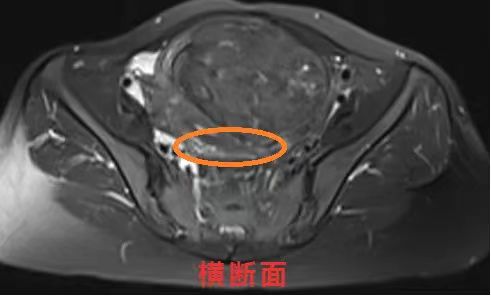

以上3张图(矢状面、冠状面、横断面)中圈出位置可见MRI:子宫后壁近宫颈处见结节状短T1信号。